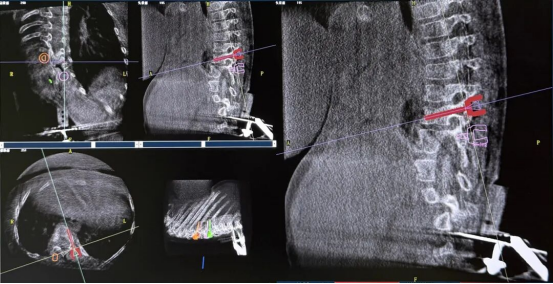

Age: 10 years

Gender: Female

Procedure: Spinal revision surgery

The patient initially underwent fixation with growing rods. However, due to rapid growth, the original fixation system could no longer accommodate her growth. A revision surgery was therefore required to adjust the fixation device and re-correct the spinal deformity.

Preoperative imaging of the pediatric patient

Pediatric spinal revision surgery is far more complex than primary surgery. The core challenges lie in anatomical adhesions and limited surgical visibility. The initial operation oftentends to induce scar tissue formation around the spinal column, which adheres muscles, blood vessels, and nerves to adhere to the spine and internal fixation devices, significantly increasing surgical difficulty. At the same time, scar-induced visual obstruction blurs the surgical field and impairs the surgeon’s ability to accurately identify spinal segments.

Children’s bones are softer than those of adults, and the initial surgery may have already caused some degree of bone damage. During revision procedures, this further increases the difficulty of implanting internal fixation devices. Improper screw depth or angulation can easily lead to implant loosening and compromise surgical outcomes

The combination of three-dimensional imaging and a surgical robot effectively addresses the critical challenges of complex anatomy and the need for high-precision localization. This synergy enables visualized preoperative planning, sub-millimeter intraoperative positioning accuracy, and a significant reduction in surgical risks.

The 3D C-arm performs image acquisition and 3D reconstruction.

Robot-assisted screw insertion path planning

Robot-assisted precise precise screw placement.